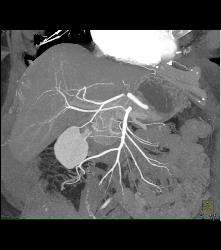

Diagnosis

Right Hepatic Artery Arises Off the Superior Mesenteric Artery (SMA) and Left Hepatic Artery Arises Off the Aorta